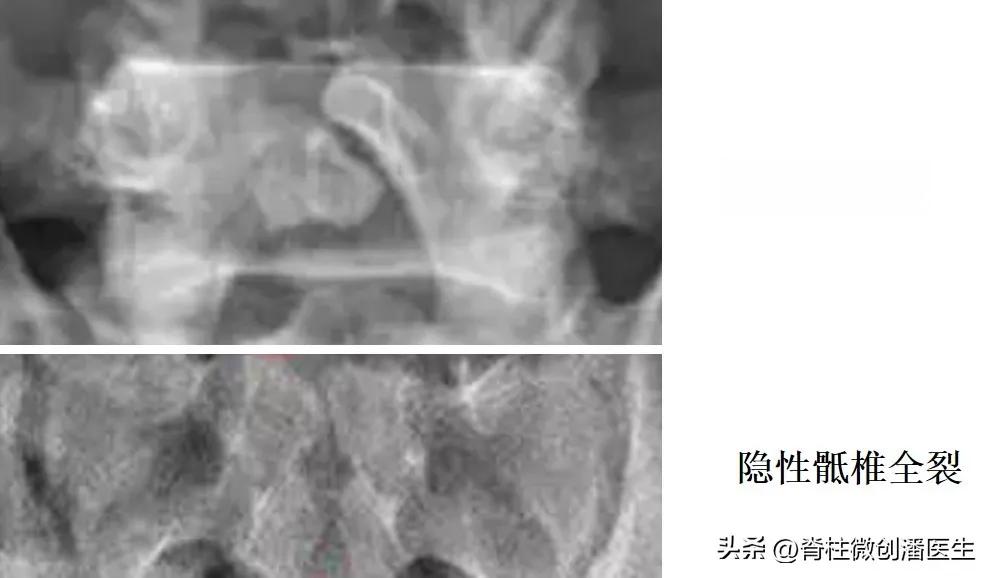

隐性脊柱裂是一种常见的脊柱发育异常,与骨折有着本质的区别。它是指脊柱椎板未能完全闭合,但椎管内容物并未膨出。这种状况多见于腰骶部,通常在X光检查或其他影像学检查中偶然发现。

诊断隐性脊柱裂主要依靠体格检查和影像学检查。医生可能会发现腰骶部皮肤有色素沉着、毛发生长异常,或下肢力量减弱。X光检查可以显示脊柱之间的裂隙,而CT和磁共振检查则有助于了解周围软组织的情况。